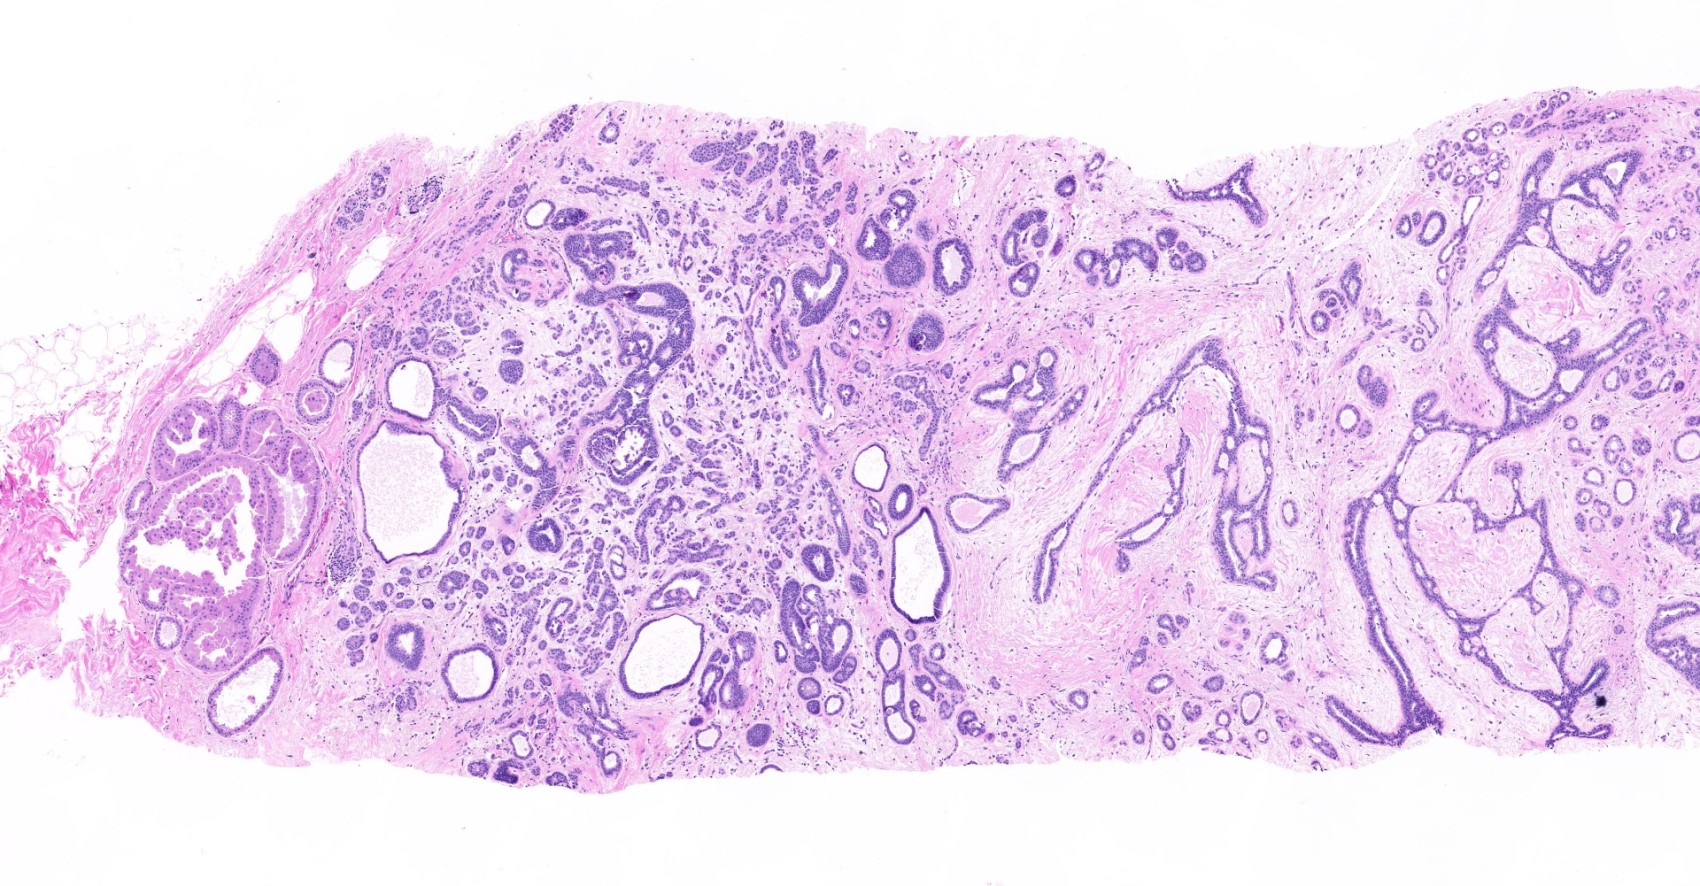

Microscopic (histologic) description

- Histologic grading is based on the Nottingham / modified Bloom & Richardson Score (Histopathology 1991;19:403):

- Histological features of IBC NST vary considerably from case to case and even within the same case

- Margins vary from highly infiltrative, permeating the surrounding tissue, to continuous pushing margins

- Architecture varies from sheets, nests, clusters, cords or individual cells (but lacks the cytomorphological characteristics of invasive lobular carcinoma)

- Tubular formations are prominent in well differentiated tumors but absent in poorly differentiated tumors

- 2 distinct growth patterns exist:

- Large and solid nests or syncytial infiltrative growth pattern with little associated stroma and an expansive growth that compresses the surrounding stroma (e.g., most basal-like breast cancers)

- Tumors characterized by small cancer nests accompanied by marked fibrosis (desmoplastic / scirrhous); this type diffusely infiltrates the surrounding tissue as an irregular shaped spiculated mass

- Calcification in 60% of cases, variable necrosis

- Elastosis involves stroma, wall of vessels and ducts and causes grossly noted chalky streaks

- Often ductal carcinoma in situ (DCIS) (up to 80%)

- In some cases, DCIS is extensive

- Associated DCIS is usually of same nuclear grade as the invasive carcinoma

- Perineural invasion (28%)

- No myoepithelial cell lining (as seen in DCIS or benign lesions)

Microscopic (histologic) images

Contributed by Julie M. Jorns, M.D., Kristen E. Muller, D.O., Gary Tozbikian, M.D. and Emad Rakha, M.D.